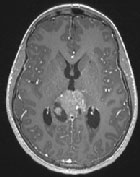

Apparences trompeuses

Cancer du SNC

Cas Clinique

Source : NeuroScoop.net - Actu'Hebdo décembre 2016

Dr Julien Boetto CHU - Montpellier

Données cliniques : Garçon, 14 ans ; Pas d’antécédent personnel ou familial ; Tableau d’hypertension intracrânienne progressif depuis 1 mois ; Vomissements itératifs ; Réalisation d’un bilan d’imagerie cérébrale...